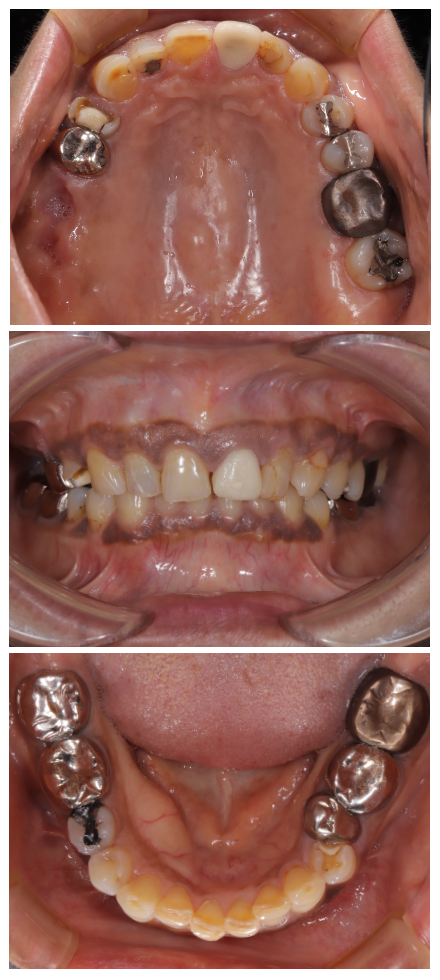

まずは、患者様の「現状の把握」から始めます。資料収集を正確に行うことにより、正確な診断が可能となり、現状の状態になっている原因を知ることができます。資料収集は歯だけではなく、多角的に顔貌から口元も含めトータル的に行います。

尚、こちらに掲載している写真や画像等は、それら資料収集の内容の1部です。皆様に視覚的にご理解頂きやすい資料のみ掲載しております。

以下症例ですが、写真を見て頂ければわかるように、赤唇部分が薄く、口角の上がり方に左右差あることがわかります。単純に歯を治療するだけでは、この状態を正常な形に整えることはできません。

また、噛み合わせにも問題があり、1部の歯は歯茎が下がっていることも分かって頂けると思います。

当院では、これらの資料収集で終わらず、以下のような骨格系の計測も実施します。

性別別に平均値が存在ます。その平均値からどれだけ逸脱しているかを調査することにより、正しい位置への補正を行うべきであるかも知ることができます。単に検査をするだけでは、意味がありません。検査を行い、そこで得た資料を歯科医師がしっかり精査を行い、現在の状態を認識しなければ、本当の意味での良い治療は提供できないと考えております。

上記のデータは資料収集の一部のデータですが、これらの資料等を集め、当院では患者様の「現状の把握」を行います。

結果この症例における現状を以下のように把握することができました。

これらの資料収集から得られた結果に基づいて【診断】=原因の究明を行って行きます。 本症例の診断結果は、以下となりました。

本症例においては、これらの改善及び治療を行っていく治療計画を立て、患者様の希望要望をお伺いしながら、治療ゴールと順序を以下のように決定をしました。